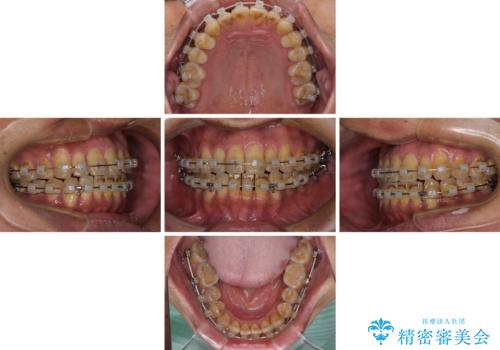

- 矯正装置

- クリアブラケット

骨格のズレが顕著であると診断され、マウスピース矯正では奥歯の咬み合わせが整えにくいと判断し、ワイヤー装置による矯正治療を行うこととしました。

上下の叢生は速やかに改善できましたが、右側のクロスバイトの改善に1年以上の期間を要しました。